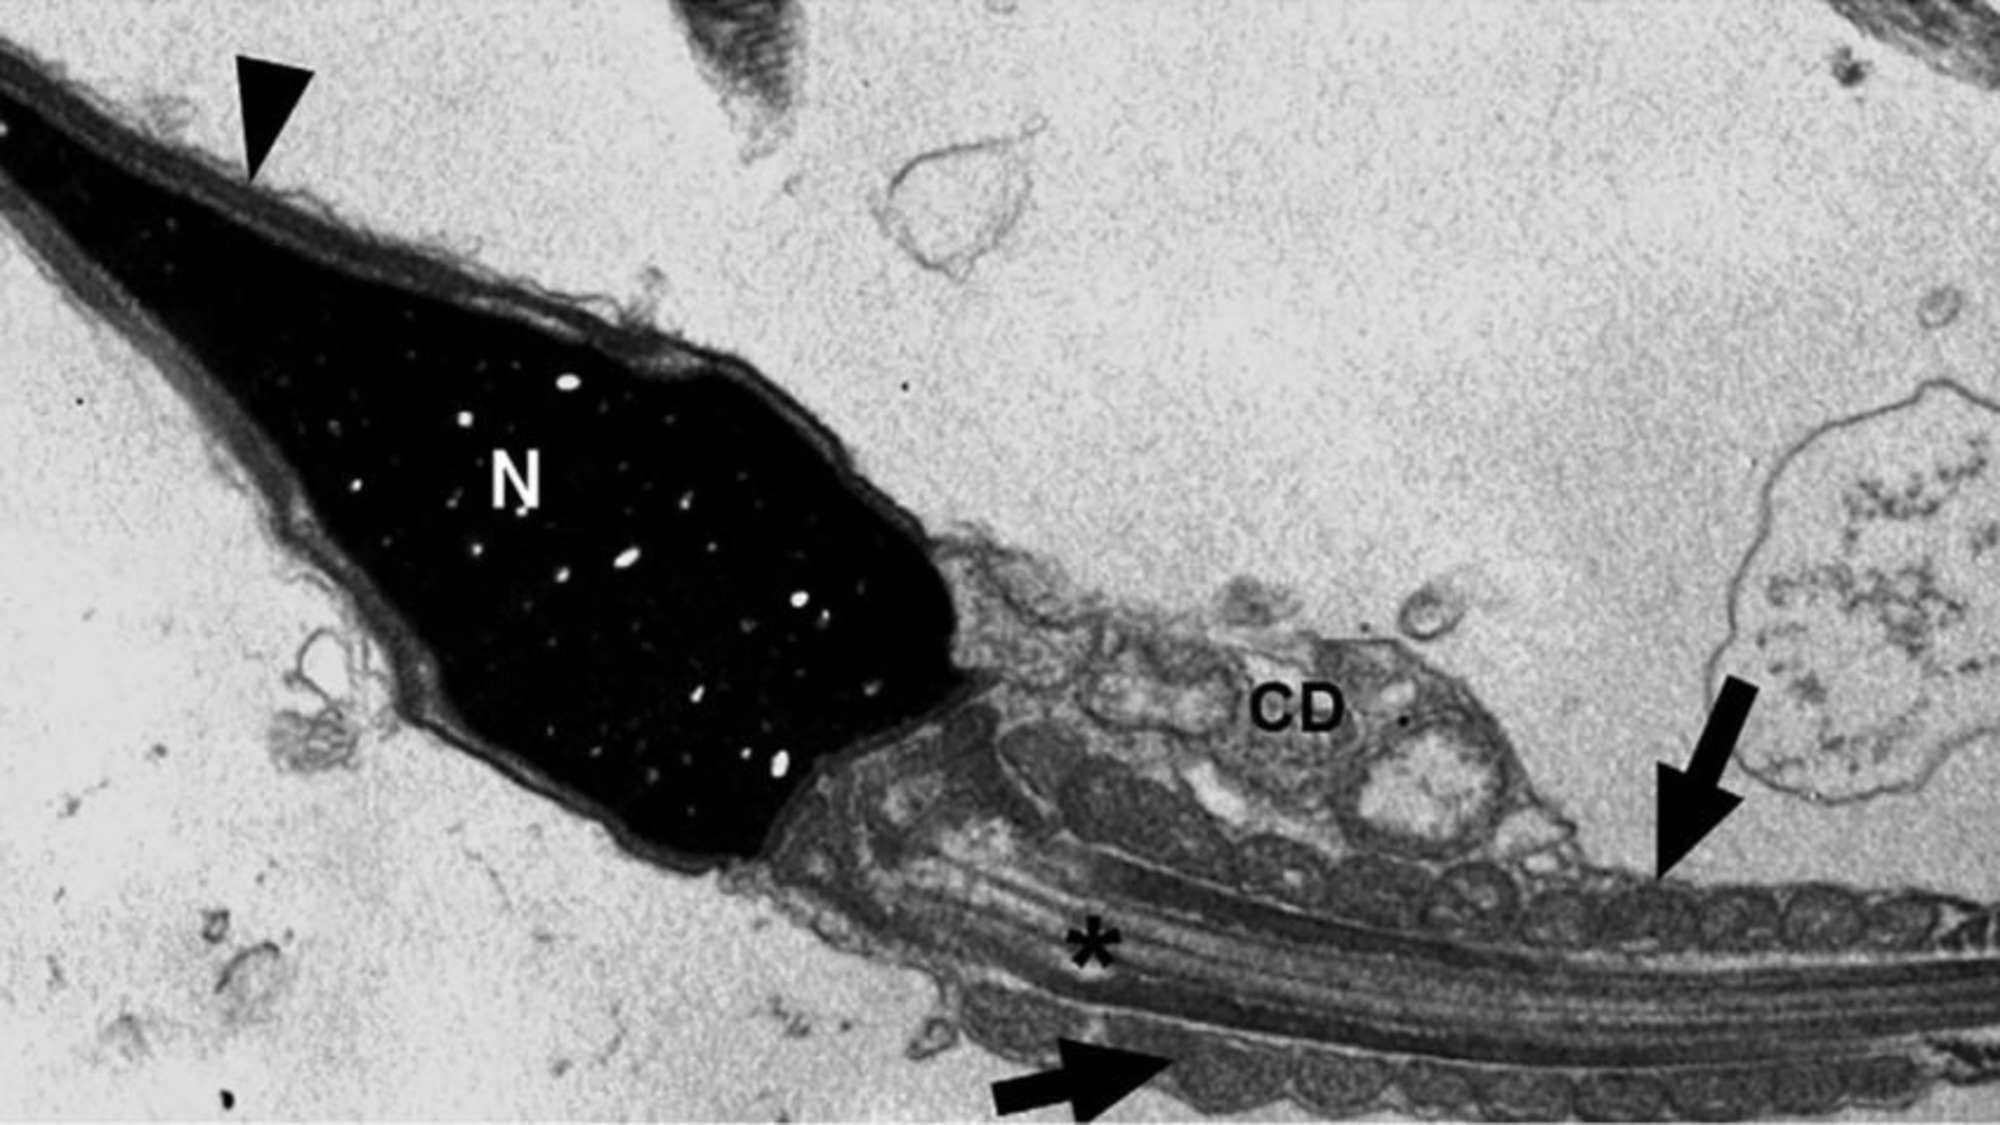

Impacto no Sistema Reprodutivo: A pesquisa analisou espermatozoides de 13 homens que tiveram COVID-19. Em 72,7% dos casos moderados a graves, o vírus foi detectado nos espermatozoides até 90 dias após a alta. No total, 69,2% dos pacientes apresentaram o vírus intracelularmente.

Mecanismo Imunológico: Os espermatozoides mostraram produzir “armadilhas extracelulares” baseadas em DNA para neutralizar o vírus, uma função imunológica inédita para essas células.